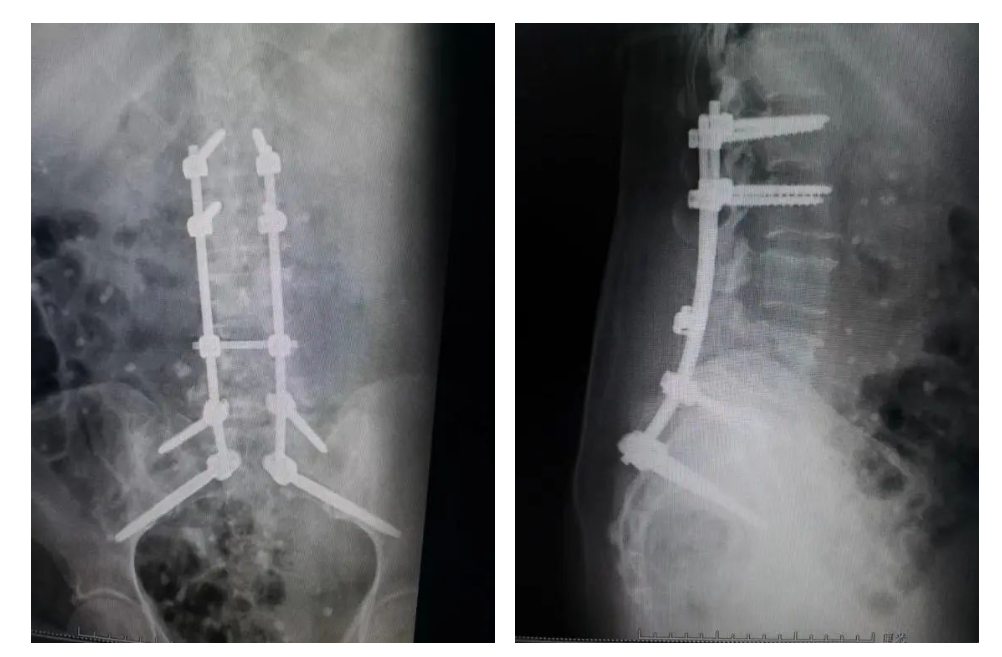

德康S2AI骶髂釘?shù)呐R床應(yīng)用展示